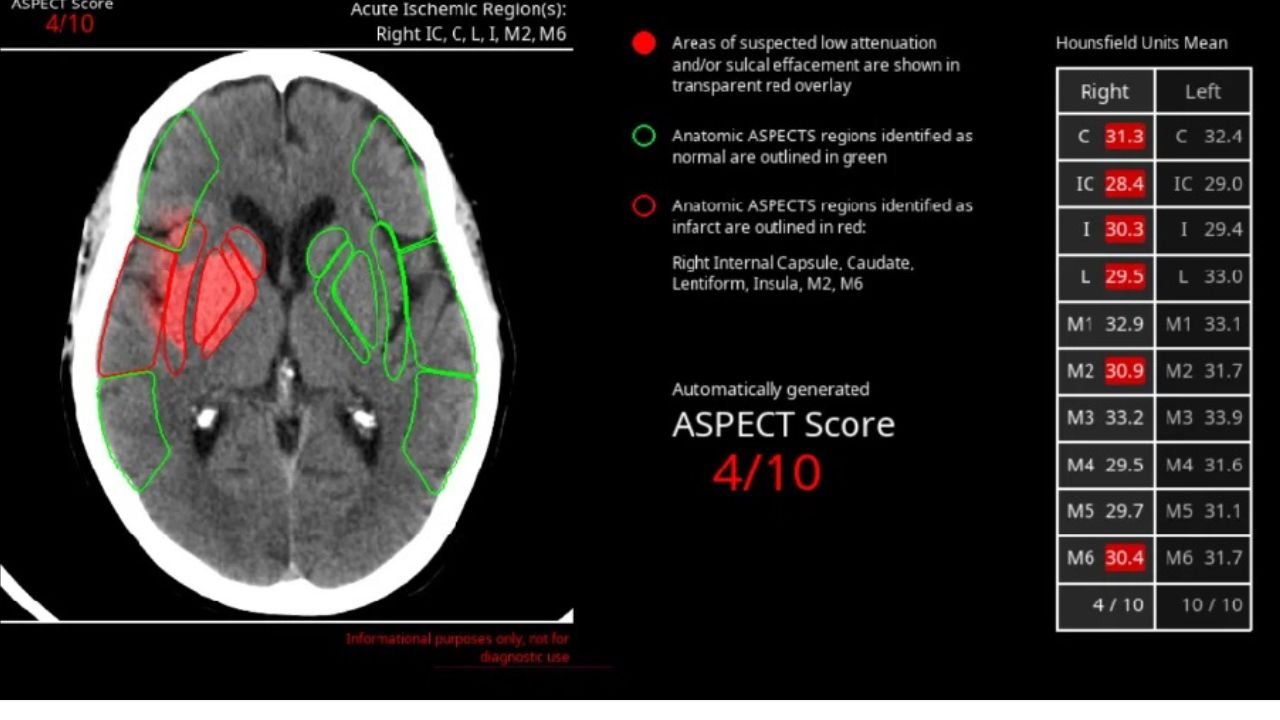

Avicenna.AI's product uses image-trained deep learning to identify, detect and quantify "life-threatening" pathologies in radiology labs. Radiologists often perform initial imaging scans to find early indicators of disease, which can be confirmed later on. But some symptoms might indicate critical, life-threatening conditions.

The Avicenna.AI platform is trained using CT scan imagery used by radiologists to triage patients presenting symptoms, before any diagnosis has become clear. The AI software has two variants: one to identify brain trauma and risk of stroke, and the other to assess chest symptoms.

Avicenna.AI's platform is employed to classify the severity of patient ailments, helping radiologists determine whether the patient's life is at risk.